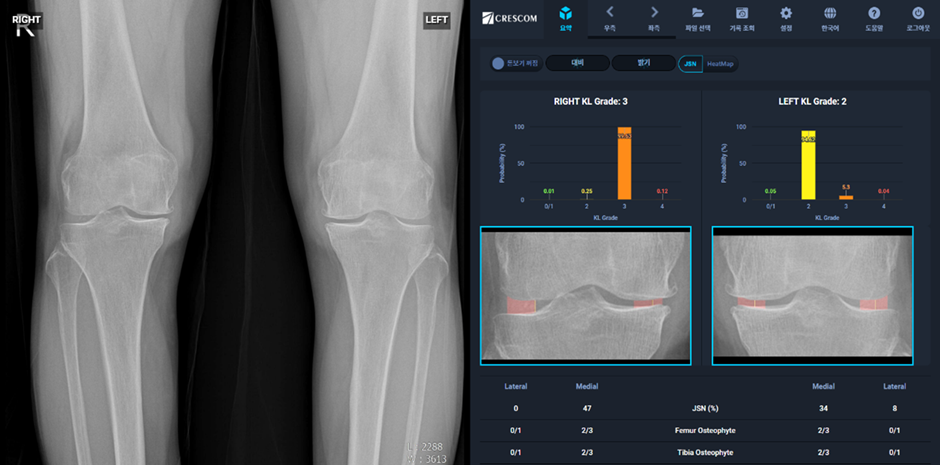

MRI, X-ray 등의 의료 영상 데이터를 AI로 분석하면 무릎 정렬 상태를 정밀하게 측정할 수 있으며, 이를 통해 관절염의 진행 단계를 예측하는 것이 가능해진다. 딥러닝 알고리즘을 이용하면 정상 정렬과 비정상 정렬을 자동으로 분류하고, 관절염 발생 위험을 정량적으로 평가할 수 있다.